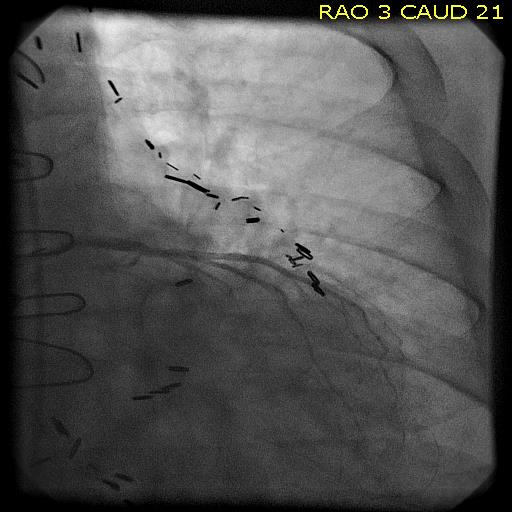

Patient is a 77 year old man with history of HTN, hyperlipidemia, former smoking, and CAD with CABGx5 and bilateral lower extremity bypasses who developed unstable angina consisting of neck and throat pain. He underwent catheterization at an outside hospital and found to have 100% LAD occlusion, a diseased, small patent left main and left circumflex (the profunda femoral artery of the heart!), 100% RCA occlusion, a patent but diseased SVG to distal RCA, and a patent LIMA graft to distal LAD but with severe plaque and near occlusion of his proximal left subclavian artery.

He had an NSTEMI. His vitals signs stabilized in the coronary care unit and he was sent to a telemetry floor. Whenever he walked, he would get the jaw pain, and this would also occur sporadically while recumbent.